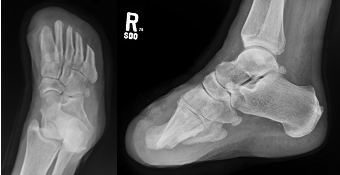

Thus, it is paramount that we treat foot ulcers in an expeditious manner for these patients. This requires podiatrists to work in a multidisciplinary team, making sure there is adequate arterial inflow, infection management, and optimization of any underlying medical conditions. Once this has been established, one should apply orthoplastic techniques to address the soft tissue deficits and correct any underlying musculoskeletal abnormalities with the goal of achieving a fully healed, plantigrade, functional foot.19